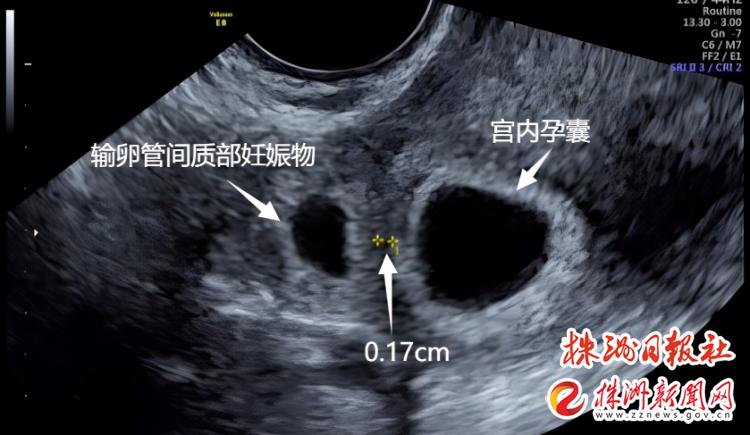

宫内有一个正常的活胚胎之外,切除的那一侧的输卵管间质部(输卵管与子宫相连接的部分,也是输卵管最狭窄的位置)似乎还有个胚胎,而且,两个胚胎相距仅仅只有0.17cm。

何主任充分考虑到汪女士的顾虑,组织生殖科、超声科、麻醉科进行MDT讨论,充分评估手术的利与弊,预估手术的风险性,术前超声评估两个孕囊最近的距离仅仅0.17cm,要在不伤到宫内孕囊的基础上清除宫外的妊娠组织,手术难度非常大,但汪女士宫外的妊娠物超声提示也有即将破裂的征象,不及时手术,一旦破裂,危及的就是汪女士本人的生命了。所以在做好各项准备后,何主任为汪女士实施了腹腔镜下手术,手术中发现输卵管间质部的妊娠组织距离破裂仅剩一层菲薄的组织,与术前的超声完全吻合。